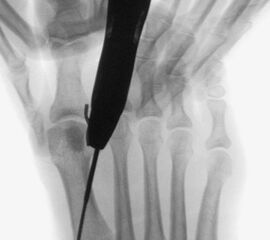

• Die Operationsplanung erfolgt anhand der Röntgenaufnahmen des Vorfußes unter Belastung in 2 Ebenen. Für die Verfahrenswahl sind wichtig der Intermetatarsalwinkel und die Breite des Os metatarsale, der Hallux valgus Winkel, der distalen Gelenkflächenwinkels (Distal Metatarsal Articular Angulation - DMAA), des Metatarsaleindex und Sesambeinposition (Abb. 1).

• Bildverstärker für intraoperative Kontrollaufnahmen 3.

• Bildverstärker.

• Positionierung des Bildverstärkers im 90° Winkel zur Fußlängsachse (Abbildung 4).

Die Fräse wird auf eine Drehzahl von 3000 – 5000 RPM eingestellt.

• Falscher Zugang, daraus resultierend falsche Osteotomieebene.